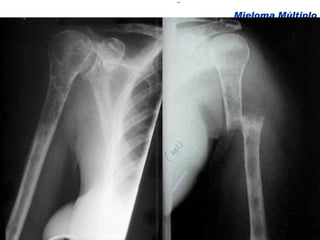

Comprometimento Ósseo

Dor ossea Presente em 2/3 dos pacientes com mieloma: dorso e tórax Agravada pelo movimento. Dor persistente pode indicar fraturas nas vértebras Manifestações clínicas Medeiros, C. R in Zago, M.A et al, Hematologia; fundamentos e prática, 2001 Hoffman Hematology 5th Edition, 2008

Dor ossea Presenteem 2/3 dos pacientes com mieloma: dorso e tórax Agravada pelo movimento. Dor persistente pode indicar fraturas nas vértebras Manifestações clínicas Medeiros, C. R in Zago, M.A et al, Hematologia; fundamentos e prática, 2001 Hoffman Hematology 5th Edition, 2008

Doença Óssea Alterações Radiológicas e Bioquímicas Kyle, 1975 Mieloma Múltiplo Nenhuma 49 19 Alteração radiológica Pacientes % Osteopenia (só) 12 5 Lesão lítica (1 local) 56 22 Lesões líticas (mais que 1 local) 101 39 Fratura vertebral 95 37 Outras fraturas patológicas 21 8 Hipercalcemia 54 21 Fosfatase alcalina elevada 47 18